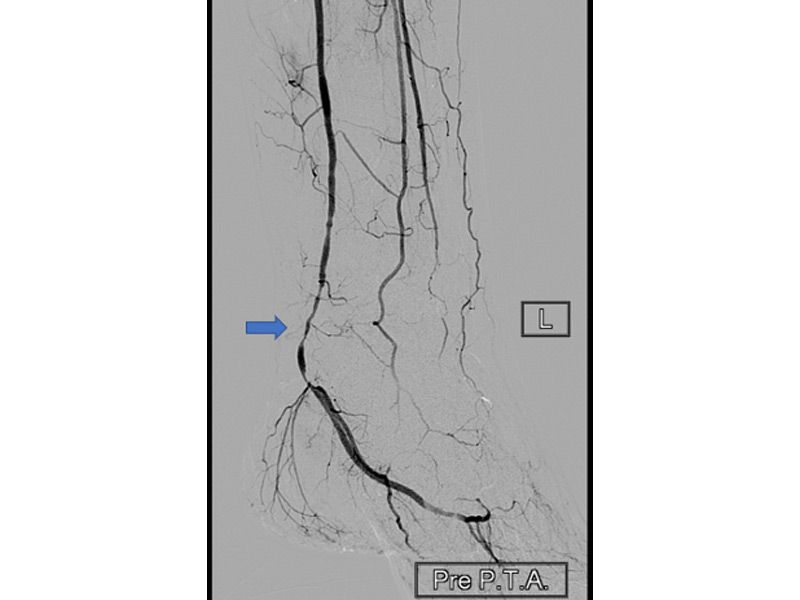

Πραγματοποιήθηκε αγγειογραφία, η οποία ανέδειξε στένωση στην οπίσθια κνημιαία αρτηρία.